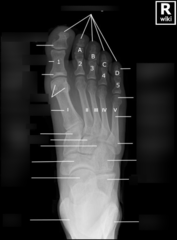

Metatarsals

Cuneiforms

Proximal phalange

Sesamoid bones

distal phalanges

MTP joint

Calcaneus

Navicular

IP joint